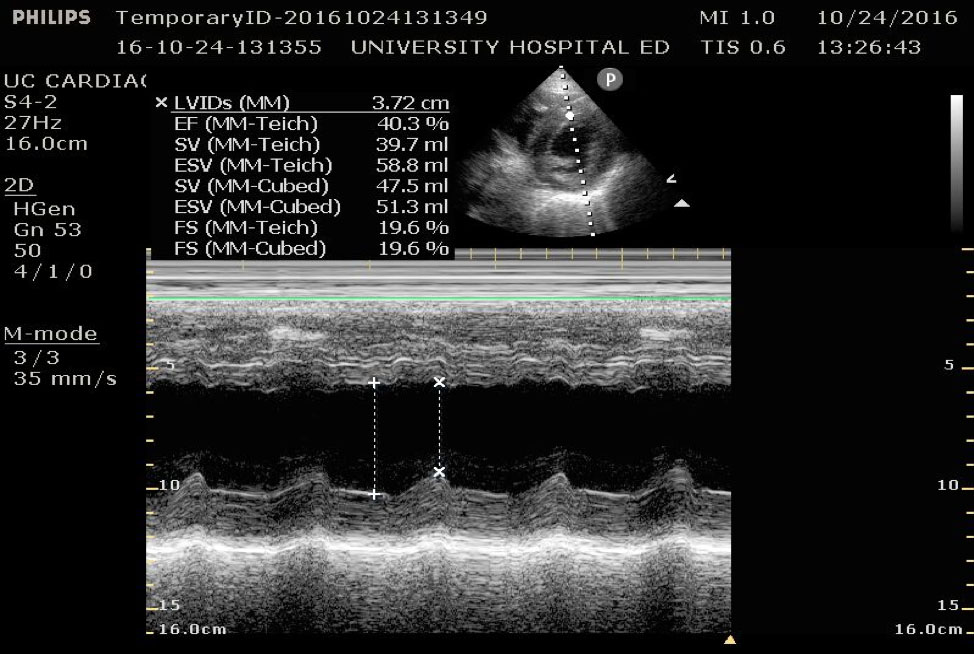

Fractional Shortening

Fractional shortening can be used to estimate EF. This is performed by placing an M-mode spike through the anterior and posterior walls of the LV at the mid-LV in the parasternal short axis view. In M-mode, the diameter of the left ventricular cavity is measured in end-diastole (LVEDD) and end-systole (LVESD). One can then apply the below formula to obtain an estimation of EF%:

FS = (LVEDD-LVESD/LVEDD) x 100%

A normal EF is suggested by a percent FS between 25-45%. (Fig. 7,8)13

Figure 8. Parasternal short axis view at the mid-papillary level with fractional shortening measurement obtained using M-mode. Fractional shortening value of 19.6%, indicating hypodynamic LV systolic function.